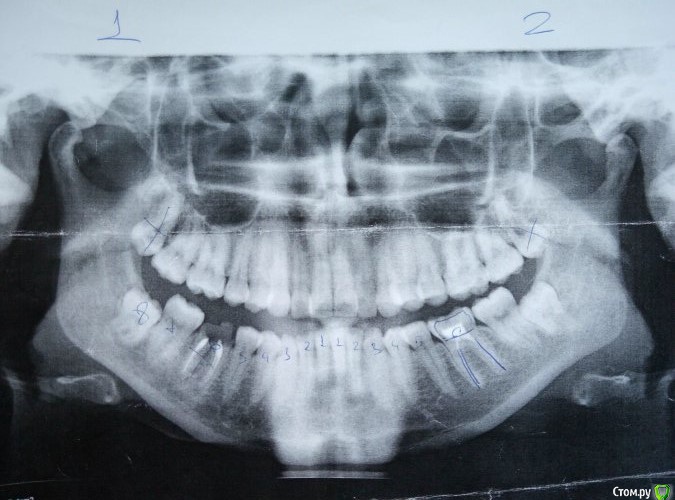

Ксения_занятый логин Опубликовано 29 марта, 2017 Автор Поделиться Опубликовано 29 марта, 2017 Прилагаю рентген Ссылка на комментарий

Brigita Опубликовано 31 марта, 2017 Поделиться Опубликовано 31 марта, 2017 по поводу Гербста - он выдвигает нижнюю челюсть вперед, в 27 лет сустав уже сформирован, на ОПТГ видно, что при выдвижении челюсти для закусок она находится в максимально переднем положении, особенно справа. Для того, чтобы определить не пострадает ли сустав от таких перемещиений - нужно сделать снимок в конструктивном прикусе, изготовить такой силиконовый сплинт, на расстояние, которое ортодонт хочет переместит челюсть и с ним уже на снимок. Посмотреть на сустав. Убедится в ложности такой идеи.Вы, возможно добьетесь какого то результата со стороны зубов, они у вас сомкнутся наконец, но заработаете очередную проблему - сустав. Ссылка на комментарий

Brigita Опубликовано 31 марта, 2017 Поделиться Опубликовано 31 марта, 2017 расширить в вашем возрасте на нужную ширину можно только опять таки с хирургическим вмешательством, операция называется остеотомия - небный шов разрывается, появляется диастема между центральными резцами, они закрываются ортодонтически и далее лечение, направленное на постановку зубов в зубном ряду.По поводу нижней челюсти и Гербста я уже писала.Идеальный вариант - это двучелюстная операция - на верхнюю и нижнюю челюсти. Ссылка на комментарий